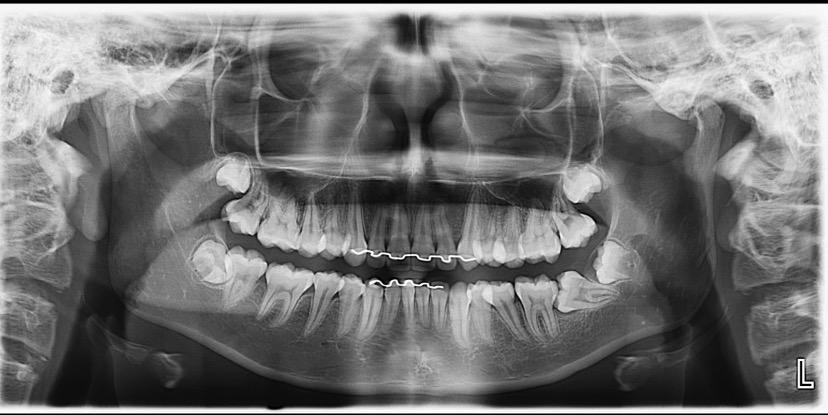

A Patologia Oral e Maxilofacial é a especialidade responsável pelo diagnóstico e tratamento de doenças que afetam a boca, mandíbula e estruturas faciais. Atua na identificação de lesões, cistos e tumores, garantindo diagnóstico preciso e tratamento adequado para preservar a saúde bucal e geral do paciente.